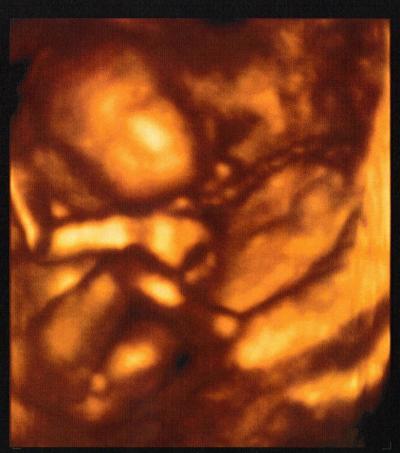

Hier mal mein zeigefreudiger Sohn in 4 D

Wow!!!! Sehr beschäftigt der kleine Mann mit seiner Nabelschnur möchte auch unbeding noch ein 4 D Bild haben, hatte das bei meiner Tochter auch.

Superknuffiges und total schoenes Bild!!!! Total goldig, wie er da die Nabelschnur in den Haenden haelt.... Und klaro, kein Zweifel, dass es sich um einen Jungen handelt!! Jungs halt, oder??!! *lach* Freu mich mit dir, GLG Agi